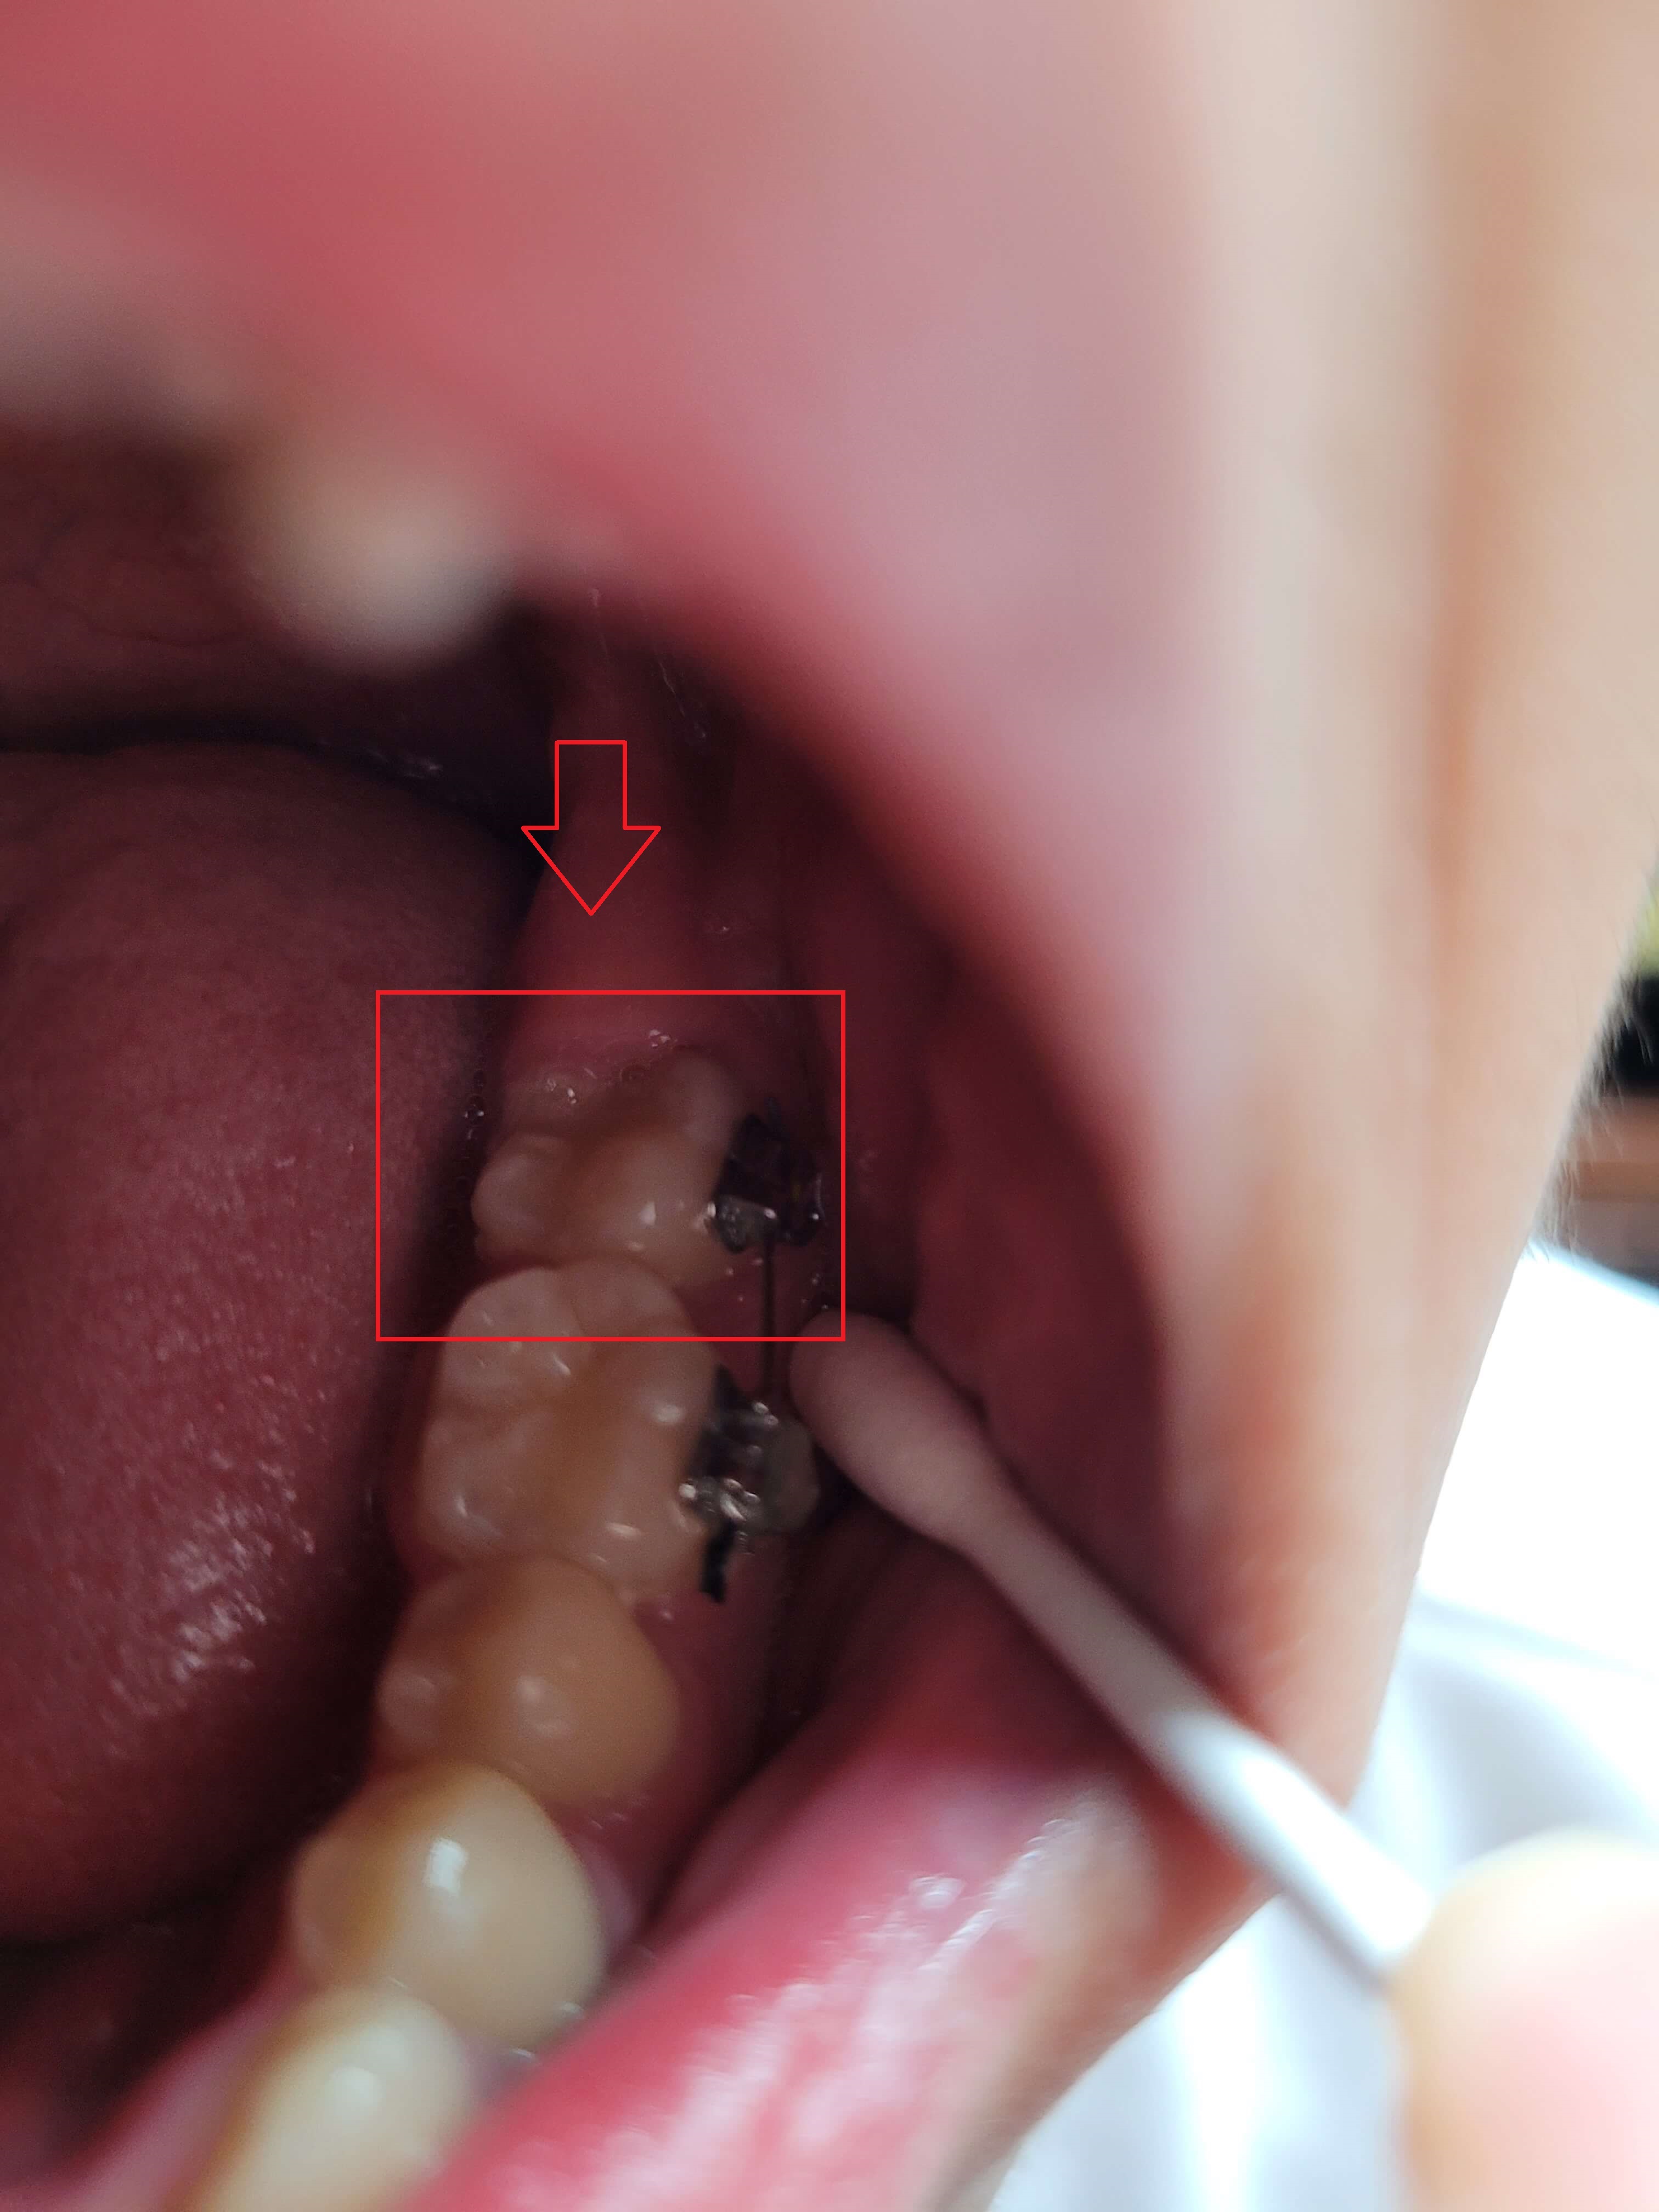

◎ 아들치아교정 전 상태확인 (가위교합사진)

- 「윗 어금니 가위교합 1개」

- 「아래 어금니 가위교합 1개」

저는 치아가 자유로이 움직인다는 것을 처음 알았습니다. 그리고 복원력이 있다는 것도 알게 되었는데요. 사진에서 보듯이 어금니가 옆으로 누워있습니다.

위, 아래 어금니가 모두 그렇는데 아래 어금니는 브라켓 설치로 힘을 주어 잡아당기고 있고 윗 어금니는 스크류를 박고 고무줄(체인)로 잡아당기고 있습니다.

▼ 아래 어금니 블라켓으로 고정후 힘을 주어 당기고 있는 모습